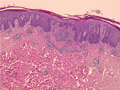

• š(1)Psoriasis (Psoriasis vulgaris)

Macroscopic image: Characteristic well-circumscribed erythematous plaques with silvery scale areseen in the flexual areas of the elbow, knee and buttock. The lesions are not itchy.